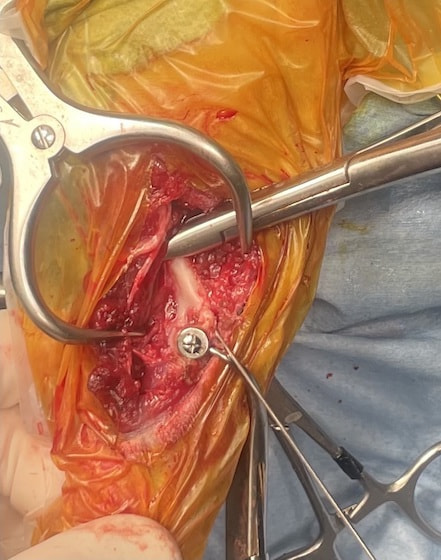

脊髄の減圧、脊柱管の再構築・安定化を目的に、片側椎弓切除術およびMatrixMANDIBLE Plateによる椎体固定を実施しました。

隣接椎体を架橋するようにプレートを設置しました。

術後レントゲン写真